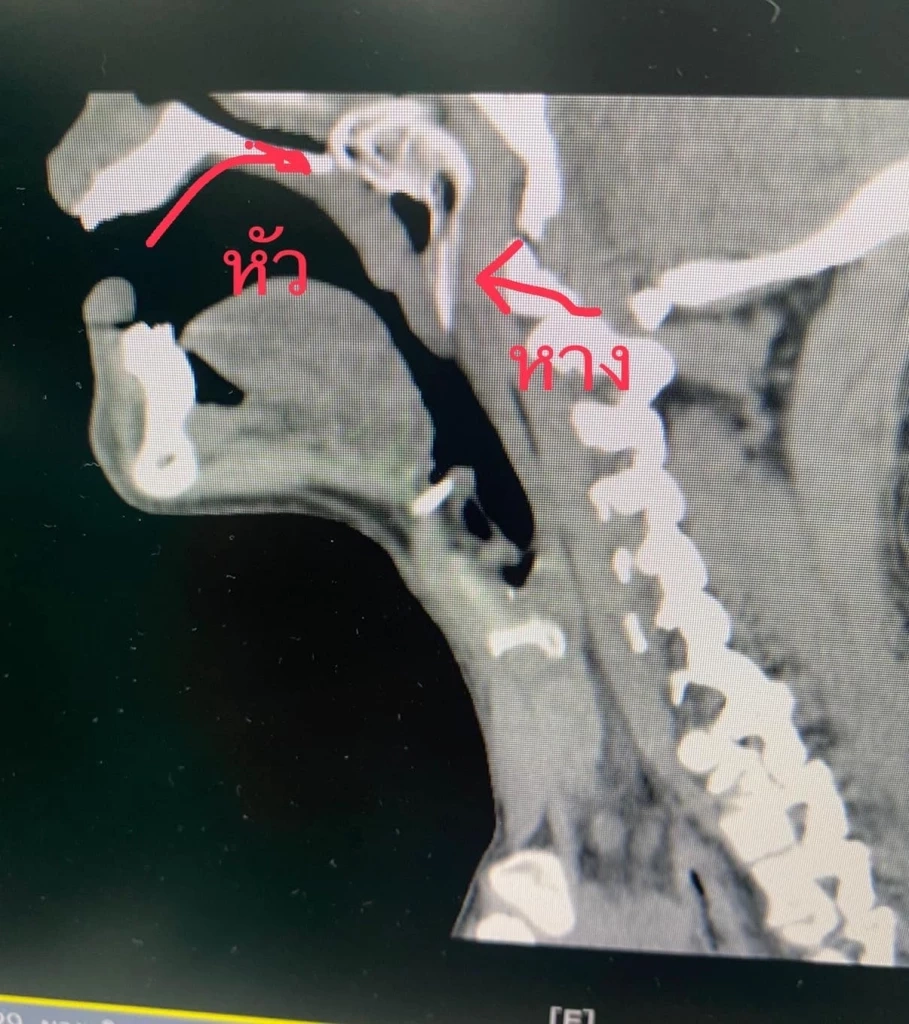

“บางสิ่ง บางอย่างก็ไม่น่าเชื่อว่ามันจะเกิดขึ้นได้ คนไข้ดำน้ำหาปลา จังหวะที่ลอยขึ้นมาจะสูดอากาศหายใจเข้าทางปาก ปลาหมอก็ว่ายเข้าไปในปากด้วย จากนั้นมันก็พยายามจะออกแต่ดันว่ายขึ้นไปหลังลิ้นไก่ แล้วหัวก็ติดอยู่หลังโพรงจมูก คนไข้เจ็บและทรมานมากๆๆ”

ที่สุดคือต้องขอบคุณทีมงานทุกๆๆคนที่ช่วยกันคิด ช่วยกันวางแผน เตรียมเครื่องมือ ทั้งกล้องที่จะใช้ส่องทางจมูก และ อุปกรณ์ที่ต้องใช้ทางปากเพราะการจะเอาปลาออกมาเป็นจุดที่ยาก จะเอาออกทางปากหรือจมูกดี เพราะต้องคิดเรื่องการย้อนเกล็ดปลาด้วย รวมทั้งเหงือกปลา ครีบปลา ก็ต้องระวังไม่ให้ครูดกับเนื้อเยื่อบริเวณนั้น เสร็จภารกิจเวรดึกกันตี 2 กว่าๆ